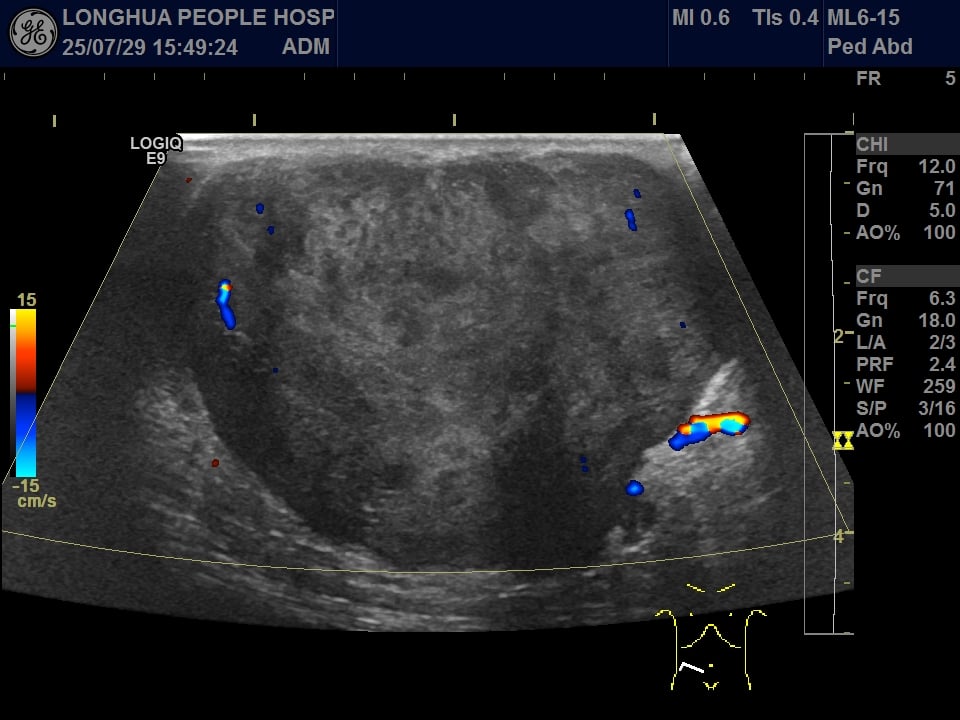

为了明确肿物的性质,医生首先为患者安排了B超检查。结果显示,在右下腹皮下探查到一个边界清晰、形态不规则的实性混合性肿块,大小约为59x53x39mm。超声提示性质待定,建议进行进一步检查以明确诊断。

B超影像显示皮下混合性肿块